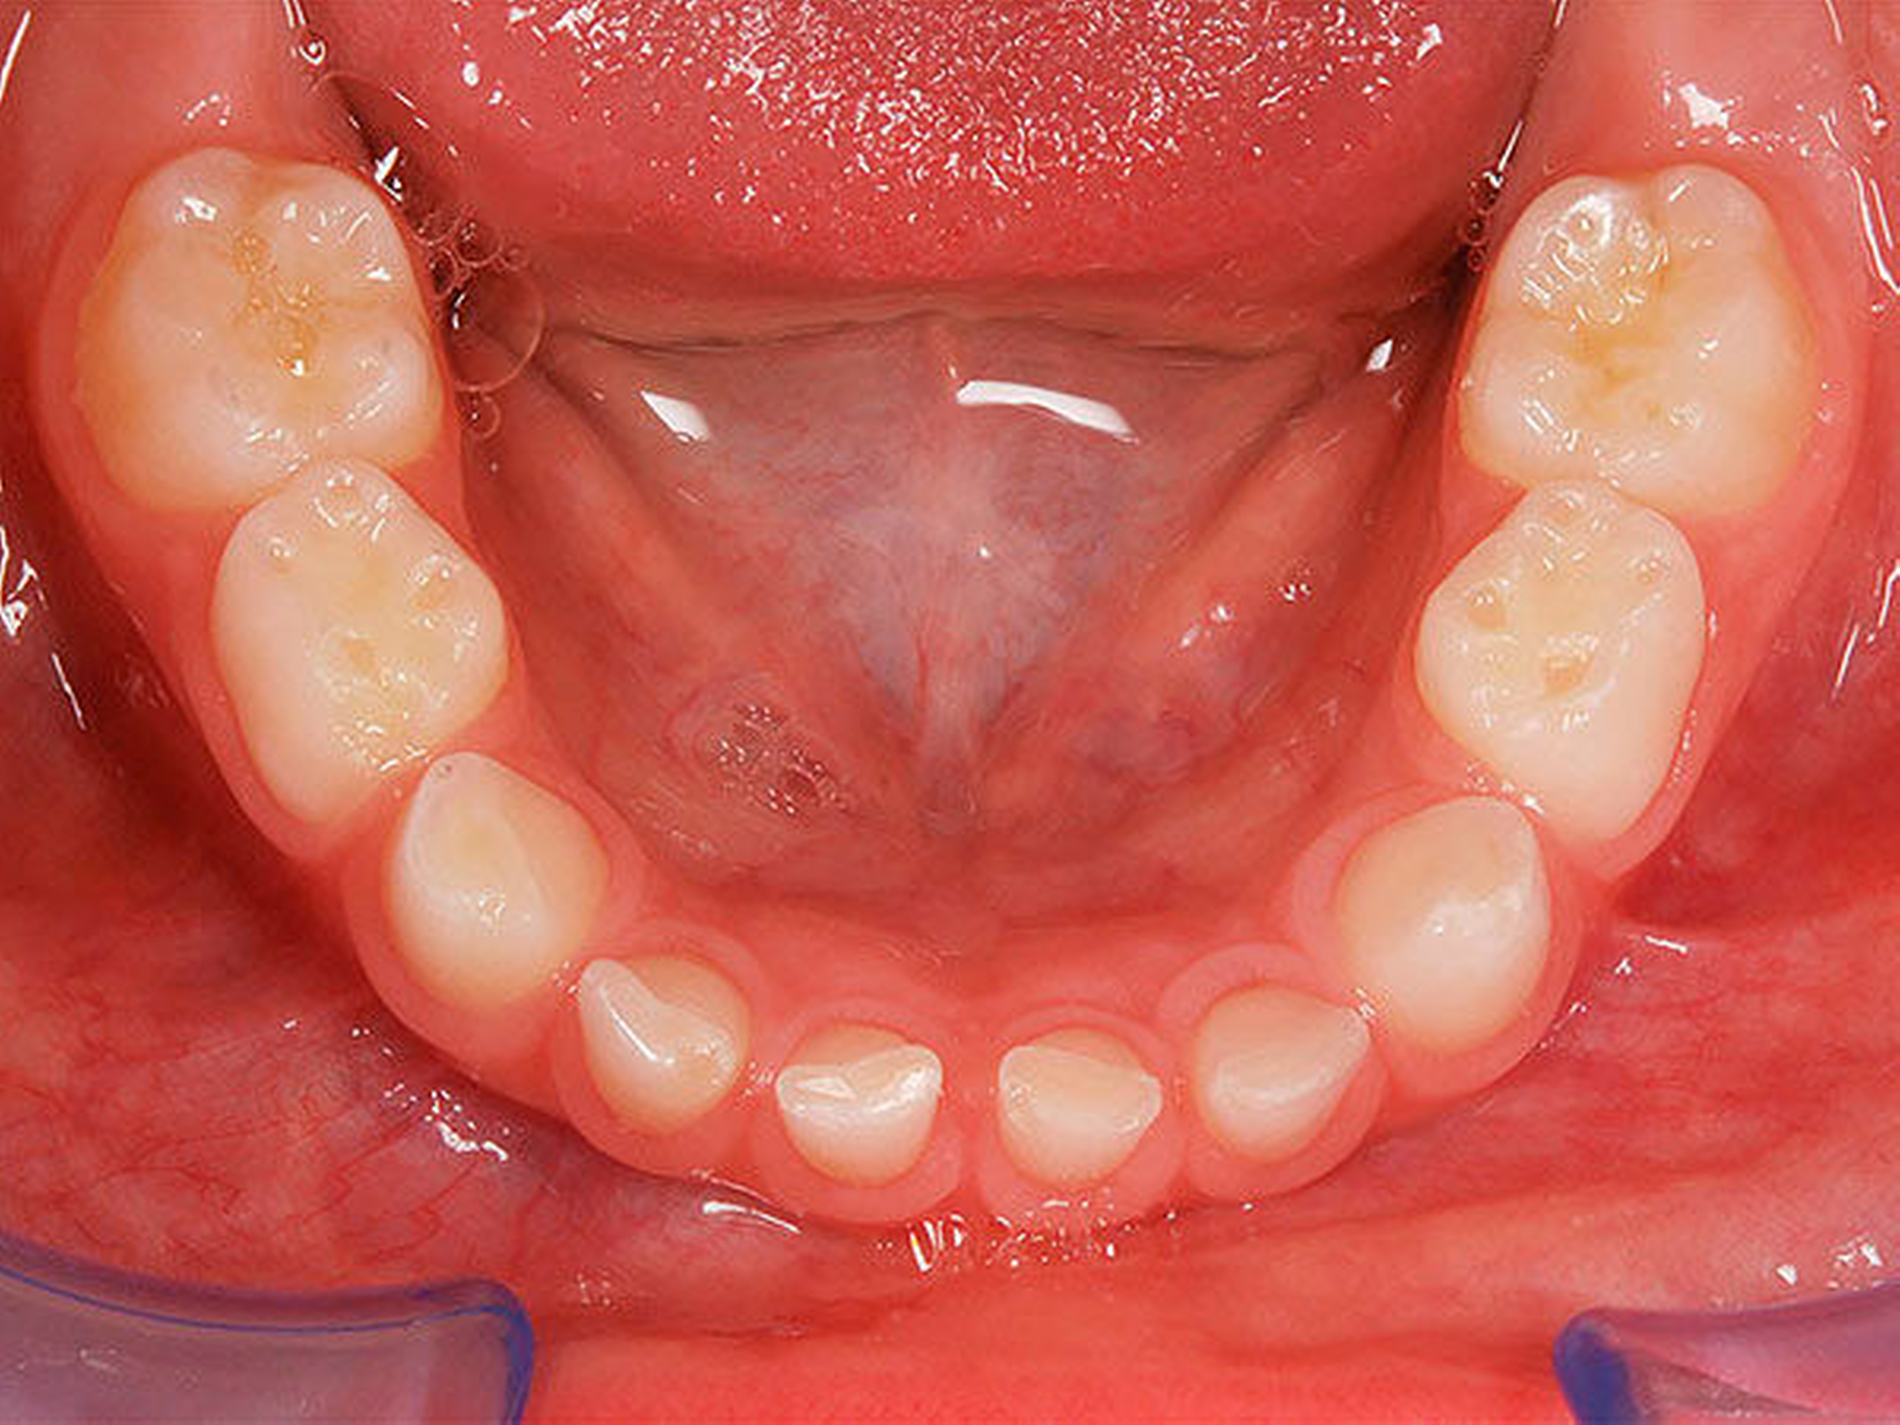

In der Gruppe des progenen Formenkreises werden Zahn- und Kieferfehlstellungen unterschiedlichster Ätiologie zusammengefasst. Diese können durch ein Missverhältnis im Wachstum beider Kiefer bedingt sein, das heißt durch Überentwicklung (Makro-/Prognathie) des Unterkiefers und/oder Unterentwicklung (Mikro-/Retrognathie) des Oberkiefers [Rakosi, 1989]. Besteht ein frontaler Kreuzbiss von Einzelzähnen oder einer ganzen Zahngruppe wird der Oberkiefer durch den Unterkiefer „eingefangen“, das heißt durch die palatinalwärts positionierten OK-Inzisiven wird das Oberkieferwachstum im Alveolarfortsatzbereich gehemmt sowie das Unterkieferwachstum „freigegeben“, da der Unterkiefer sich postnatal in sagittaler Richtung ohnehin stärker als der Oberkiefer entwickelt [Lux, 2004]. Zudem kann eine Zwangsbissführung des Unterkiefers nach ventral vorliegen [Keeling, 1998]. Diese kann zusätzlich zu einer unerwünschten Wachstumsstimulation des Unterkiefers mit nachfolgender skelettaler Manifestation führen. Mit einem therapeutisch eingestellten sicheren frontalen Überbiss (sagittal und vertikal) kann die weitere Kieferentwicklung koordinierter ablaufen (Abbildung 4). Die Anomalien des progenen Formenkreises besitzen häufig auch eine hereditäre Komponente, wobei unphysiologische Ruheweichteilbeziehungen oder Dysfunktionen den Phänotyp deutlich verstärken können. Da bei Klasse-III-Dysgnathien die skelettalen Therapieergebnisse bei frühzeitigem Behandlungsbeginn am besten sind, sollte frühzeitig mit einer kausalen Therapie begonnen werden – also sobald eine ausreichende Compliance des Patienten es zulässt, [Baccetti, 1998; Da Silva, 1998; Franci, 2004; Lang, 2001; Saadi, 2000].